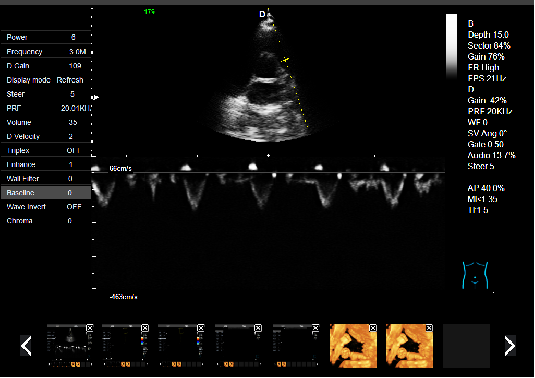

P5-VET手提式獸用彩超機(jī)心臟超聲檢查圖

心臟超聲檢查:

心臟超聲是唯一能動(dòng)態(tài)顯示心腔內(nèi)結(jié)構(gòu)、心臟的搏動(dòng)和血液流動(dòng)的儀器,對(duì)人體沒(méi)有任何損傷。心臟的各個(gè)結(jié)構(gòu)清晰地顯示在屏幕上。通過(guò)彩超的測(cè)量,醫(yī)生可了解瓣膜病變的程度以決定保守治療還是手術(shù)治療。心肌的增厚、心腔的擴(kuò)大都要依賴彩超來(lái)判斷;對(duì)冠心病,彩超能直觀顯示心肌的運(yùn)動(dòng)狀況及心功能,向臨床醫(yī)生提示心肌缺血的部位。